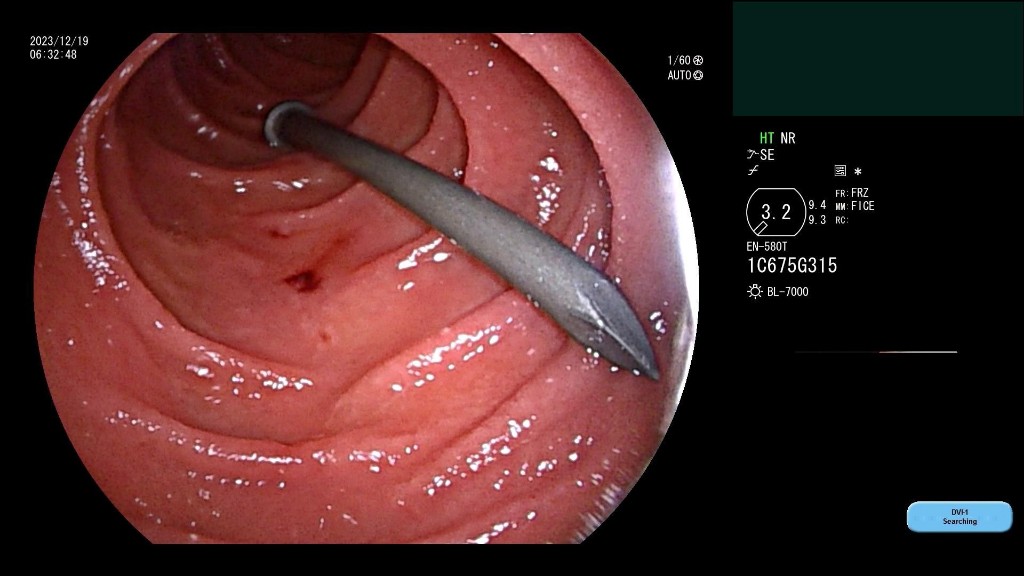

在了解患者情况后,西安市红会医院消化疾病诊疗中心消化内科副主任施育鹏以及相关医护人员当即从家中赶往医院,在此期间消化内科开启消化道出血绿色通道,为患者做腹部CT,同时联动麻醉科医生进行麻醉评估。到达医院后,为避免肠道穿孔,施育鹏医生借助小肠镜,在贲门处调转钢钉方向,用小肠镜外套管包裹钢钉头并取出,整个过程仅用时20分钟,术后患者情况稳定。

完成一场急诊小肠镜,取出小肠内的异物,需要具备多少条件?此次手术的成功,展现出西安市红会医院消化内科小肠镜水平的成熟。西安市红会医院消化疾病诊疗中心消化内科主任韩霜介绍,由于小肠弯曲,误吞的异物如枣核、绣花针等如果从十二指肠进入小肠,随时有穿孔风险,需要通过肠镜取出,而小肠镜手术需要在全麻下进行。在严重的情况下则需要通过剖腹手术移除。

19日在消化道出血绿色通道开启后,红会医院及时联动麻醉科为患者进行麻醉评估,消化内科医护人员则迅速赶往医院进行治疗,为患者争取最佳治疗时间。同时,在手术进行中,如果出现小肠穿孔情况,消化内科配备相应的内镜下止血条件,避免患者剖腹手术的风险。消化内科的医疗团队接触小肠镜案例多、技术纯熟,可以为患者提供专业的医疗服务。

“误吞异物一定要及时到医院治疗,减少制动、停止饮食,切勿等到出现明显症状后才就医”施育鹏医生介绍,他进行小肠镜检查、治疗工作十余年,及时送医非常关键,否则会面临肠道穿孔、剖腹手术的风险。